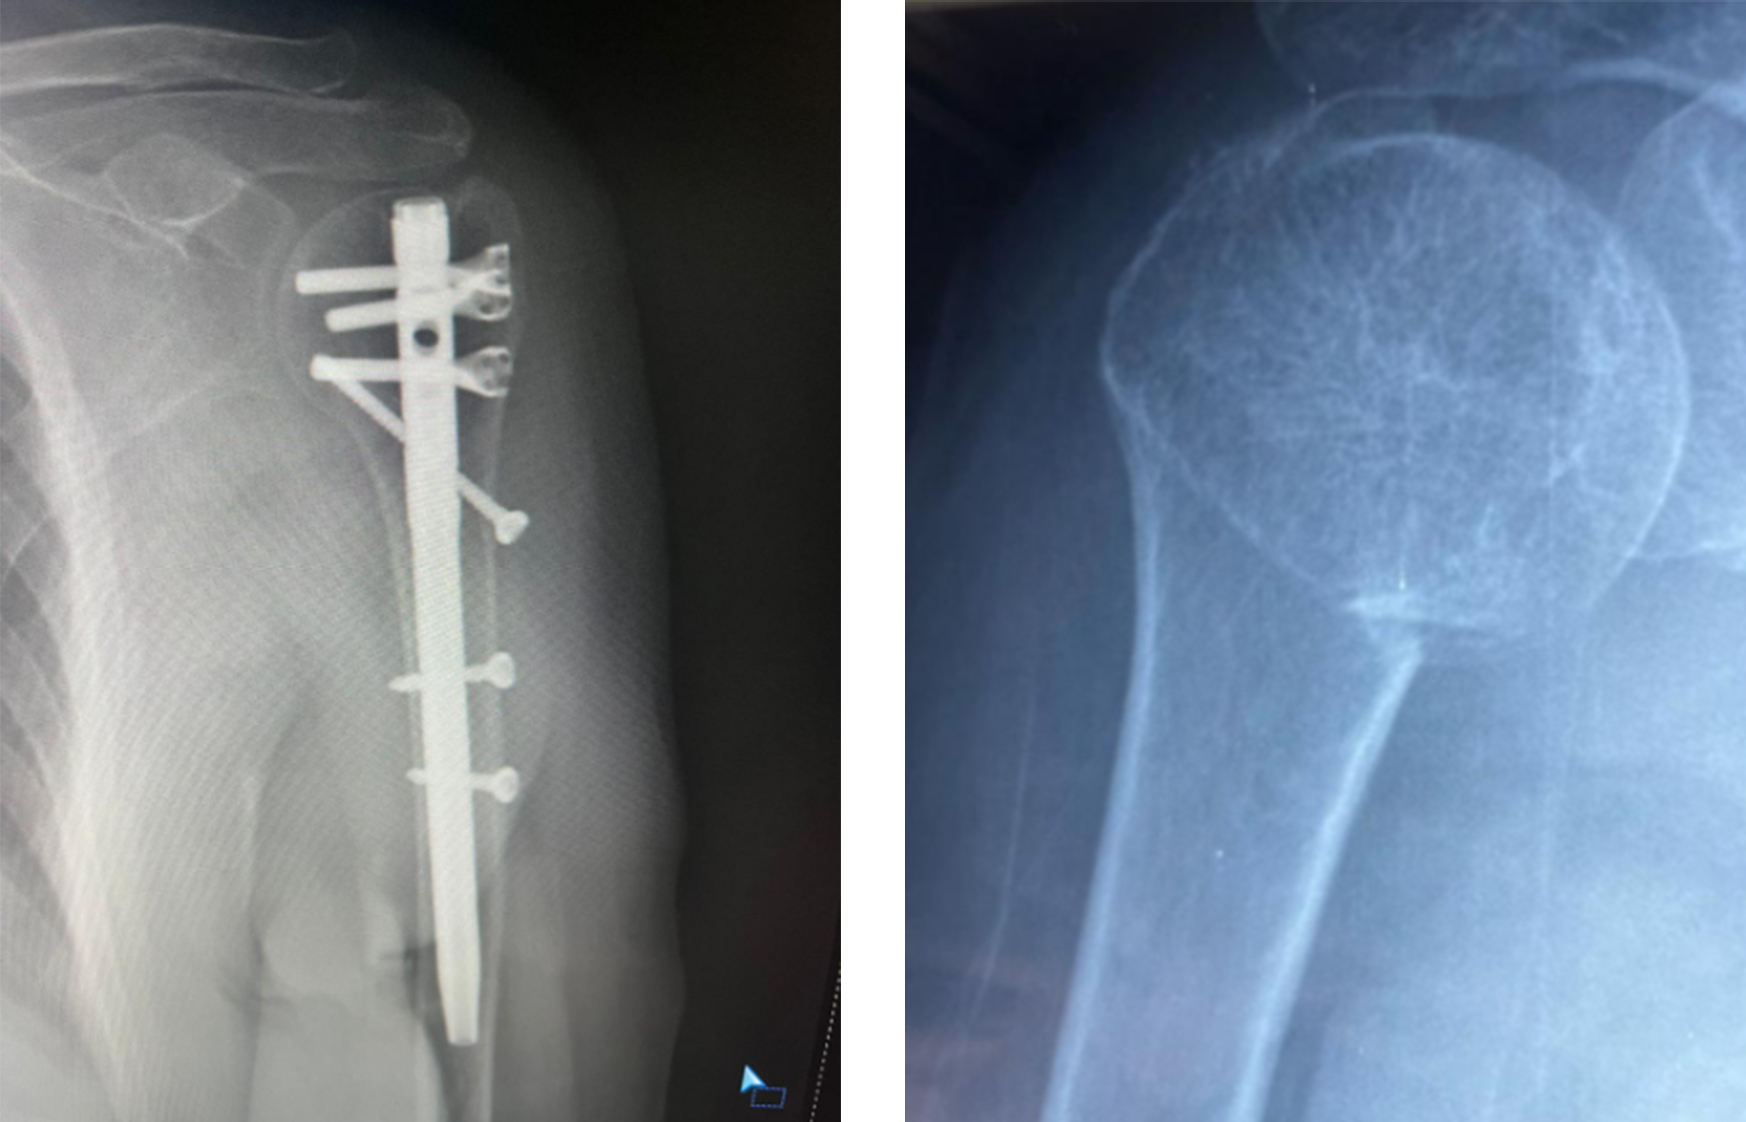

Intramedullary Nail Fixation

Intramedullêre nagelfixaasje is in minimaal invasive technyk dy't ynterne stipe leveret troch it medullêre kanaal.

humerus intramedullary nagel fixaasje ortopedyske sjirurgy.jpg

Wannear't intramedullêre nagel de foarkar hat

• Chirurgyske nekkefraktueren

• Minimale sêfte weefsel fersteuring nedich

• Bepaalde shaft-belutsen fraktueren